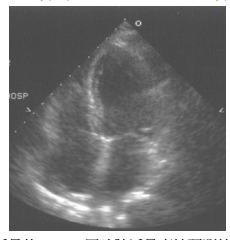

12 這張 2-D 心臟超音波圖是下列何種掃描面? (A)長軸(long axis view) (B)短軸(short axis view) (C)四室(four chamber view) (D)胸骨上(suprasternal notch view)